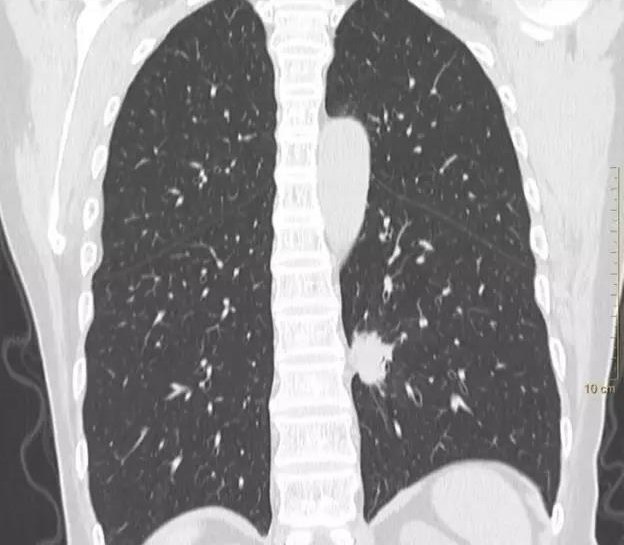

肺腺癌CT

肺腺癌CT图片

浸润性肺腺癌

肺腺癌图片

肺腺癌图片全面展示